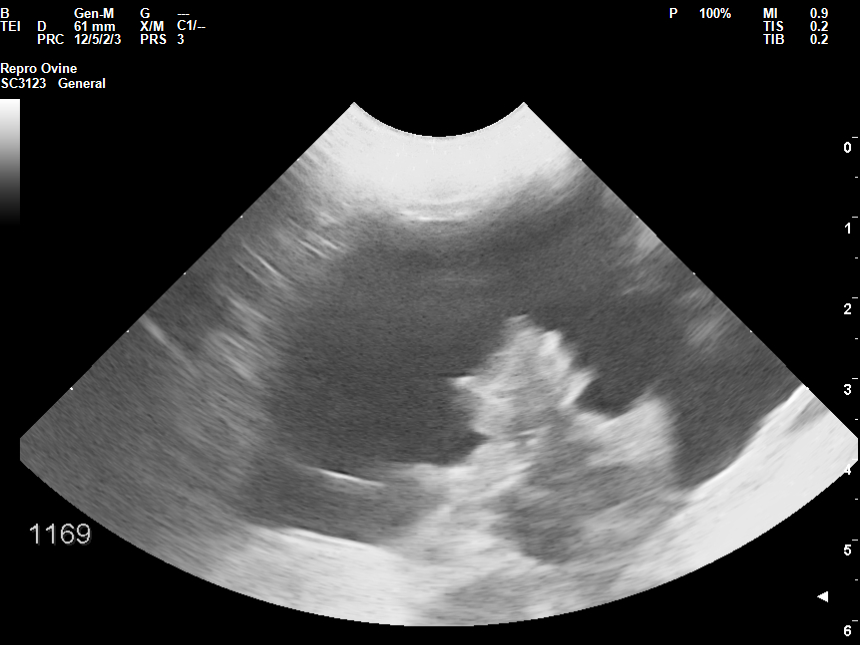

• Εξέταση όρχεων